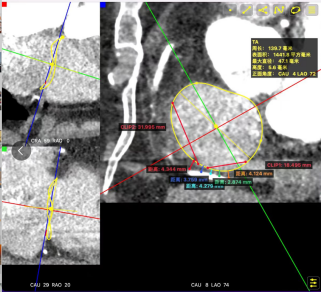

CTA Evaluation: Tricuspid annulus circumference: 13.9cm, area: 14.4cm², with low coronary artery risk.

Based on the comprehensive preoperative CT and TEE evaluation of the patient's tricuspid annulus morphology and the primary regurgitation location at the central anteroseptal commissure, it was planned to implant one 12T K-Clip® device each at the posteroseptal commissure and the anteroposterior commissure of the tricuspid annulus. This approach is intended to reduce the annulus circumference and increase the leaflet coaptation margin, thereby alleviating tricuspid regurgitation.